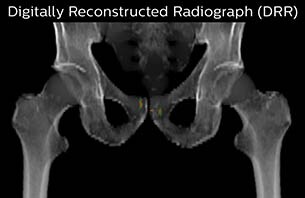

Using the mDIXON and 3D bFFE images, the RT planner marks the position of the nickel-titanium fiducial markers, and contours are transferred to the digitally reconstructed radiographs (DRRs). Reference image matching is based on these markers. “In the rare cases, where visualization of the fiducial markers fails, we do a CT to confirm their location,” Dr. Keyriläinen notes.

MR-only simulation workflow The 3D T1W FFE mDIXON sequence provides in-phase, water and fat images in one acquisition. Target and organs-at-risk are delineated on the 3D T2W TSE images. Prostate GTV is shown in orange, PTV in purple. The 3D bFFE sequence is used by the planner to mark the position of the fiducial markers (gold anchors) and contours are transferred to the digitally reconstructed radiographs (DRRs).

Based on the 3D T1W mDIXON images, MR-based density maps (MRCAT) are automatically generated. The VMAT (Volumetric Modulated Arc Therapy) plan is generated in TPS, based on MRCAT as primary image set. During the commissioning phase, dosimetric agreement between MRCAT-based and CT-based dose plans was studied and differences in the PTV dose were found to be minimal (<1% for most patients). Average difference in PTV mean values was 0.8% over the study group (n=62).

The Philips MRCAT approach for an MR-only based dose planning provides CT-like density information calculated from MR images for dose calculations, as well as high contrast anatomical T2W images for target delineation. [2-3] The MRCAT images with density information are DICOM conform and can be automatically exported to treatment planning systems (TPS) as primary image dataset for dose calculations and to generate MR-based digitally reconstructed radiographs (DRRs).